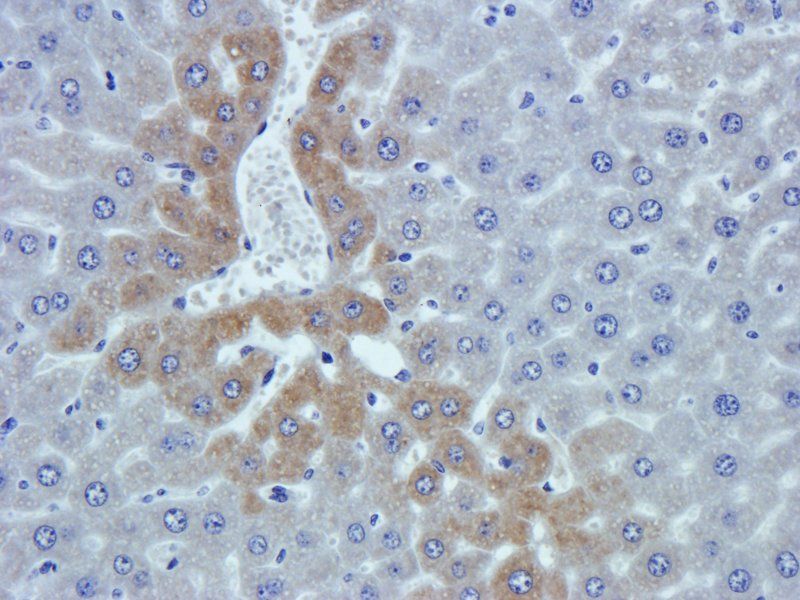

10 μg, 100 μg - Cubilin antibody [orb4997]Featured

ICC, IF, IHC-P, WB

Human, Mouse, Porcine, Rat

Rabbit

Polyclonal

Unconjugated

100 μg - PGP9.5 antibody [orb6713]Featured